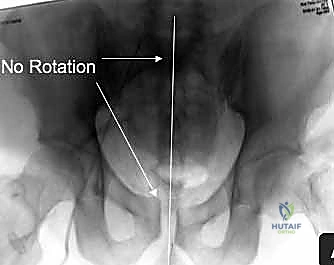

2. الأشعة السينية (X-rays): توفر نظرة أولية سريعة على كسور الحوض (AP, Inlet, and Outlet views).

3. التصوير المقطعي المحوسب (CT Scan): وهو المعيار الذهبي (Gold Standard) لتشخيص كسور الحوض والعجز. يقوم الدكتور هطيف باستخدام تقنية إعادة البناء ثلاثي الأبعاد (3D Reconstruction) لفهم هندسة الكسر بدقة متناهية قبل الدخول إلى غرفة العمليات.